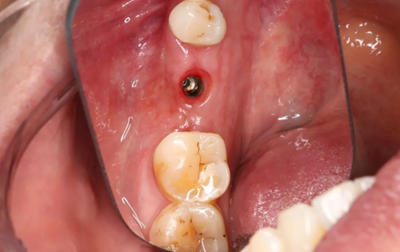

17、修復(fù)照片

袖口形成,上皮健康,遠(yuǎn)中唇側(cè)軟硬組織欠豐滿(mǎn)。

(攝于2018年5月25日)